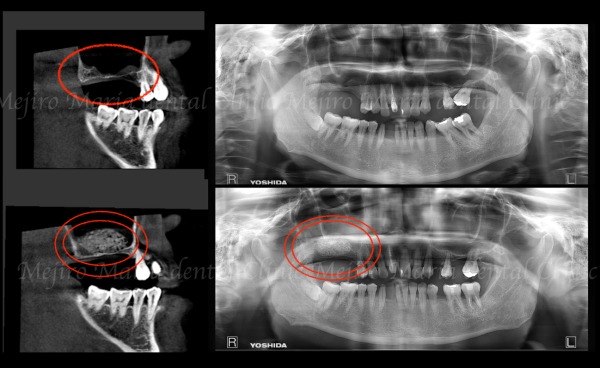

サイナスリフトでは、側方から上顎洞粘膜を挙上し、できた空間に人工骨を填入することで3〜6ヶ月後にインプラント埋入可能な骨が形成されます(赤二重丸◎部分)。

サイナスリフト後6ヶ月(抜歯から10ヶ月)で、インプラントを理想的な位置に安全に埋入できました。術後の上顎洞や歯肉にも炎症は認められません。

右上で噛む力を支えられるようになったことで前歯の負担が軽減し、同時に行っていた矯正治療により左側の噛み合わせも改善したことで、長期的に安定した咬合が期待できます。